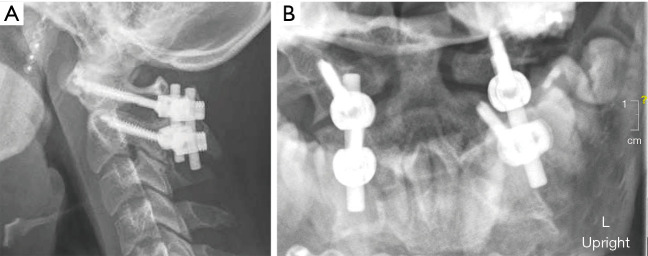

Less than 24 hours after presentation, the patient was taken to the OR for urgent management of his multiple injuries. He first underwent external fixation of his right pilon fracture, followed by C1-C2 posterior instrumentation and fusion (Figure 2). He was placed in a C-collar and transferred to the intensive care unit (ICU) post-operatively. Per our institution protocol, post-operative cervical spine CT was obtained which revealed further distraction and subluxation of the occipitocervical junction bilaterally, with a CCI of 4 mm bilaterally, a basion-dens interval (BDI) of 10 mm, and a Power’s Ratio of 1.1 (Figure 3). Due to concern for significant injury, the patient was brought back urgently to the OR for traction testing to rule out OCD.

Figure 2.

Postoperative lateral (A) and open mouth (B) C1-C2 fixation showing reduced C1-C2 interval and without evidence of transverse ligament disruption. L, left.